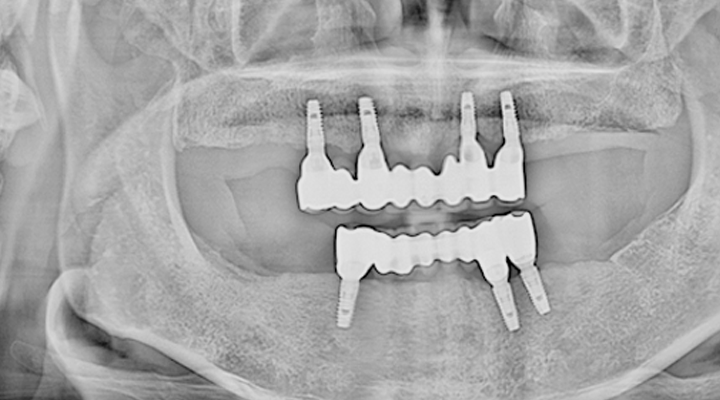

여러 개의 임플란트를 심은 뒤,

그 사이를 금속 막대로 연결해 튼튼한 지지대를 만들고,

그 위에 틀니를 안정적으로 고정하는 방식입니다.